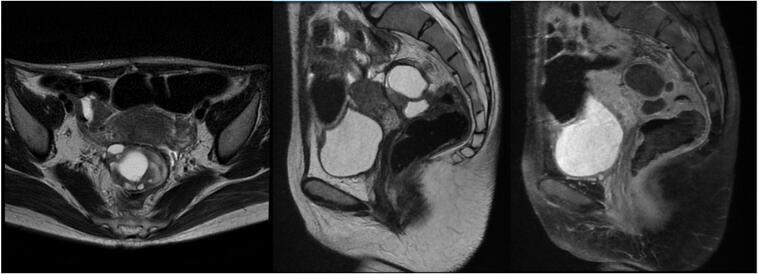

CASE PRESENTATION

We report an exceptional case involving a 22-year-old woman initially diagnosed with a malignant mixed germ cell tumor (MGCT) during pregnancy. Following surgical debulking and chemotherapy, she rapidly developed two distinct secondary malignancies within one year: enteric-type adenocarcinoma and chemotherapy-related acute myeloid leukemia (AML). Despite multidisciplinary interventions, the patient succumbed to disease progression and treatment complications.

我们报告了一例特殊病例,一名22岁女性在怀孕期间最初被诊断为恶性混合性生殖细胞肿瘤(MGCT)。在手术减瘤和化疗后,她在一年内迅速发展出两种不同的继发性恶性肿瘤:肠型腺癌和化疗相关的急性髓系白血病(AML)。尽管采取了多学科干预措施,患者仍因疾病进展和治疗并发症而死亡。